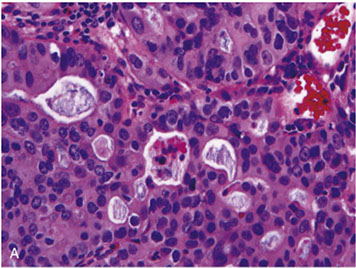

Esophageal AC organized in back-to-back glands

Micro: best predictors of findings AC in a resection specimen from biopsy are ulceration, syncytial glands with cribriform lumens, and intraluminal necrotic debris; intraepithelial neuts in areas of dysplasia and extension of neoplastic glands to b9 squamous epithelium are also highly predictive

- look like AC in other organs, having either glandular structures or mucin production

- can be classified as papillary, tubular, signet ring and can have endocrine cells, Paneth cells or predominance of mucin (not important to classify, has no real value)